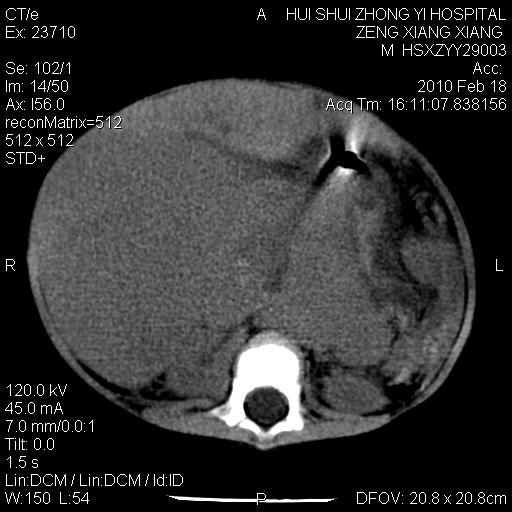

标题: PED3106:男,2岁,腹胀1月。 [打印本页]

标题: PED3106:男,2岁,腹胀1月。

定位腹膜后,肾上腺来源;

定性:恶性神经源性,肾上腺神经节母细胞瘤可能性大。

鉴别:肝母、肾母、肝脏中胚层错构瘤。

依据:年龄、有钙化,肾脏及肝脏受压移位。

肝母细胞瘤可能性大,右肾形态大体可见,不支持肾母细胞瘤,右肾移位不明显,肾上腺神经母细胞瘤可能性不大。